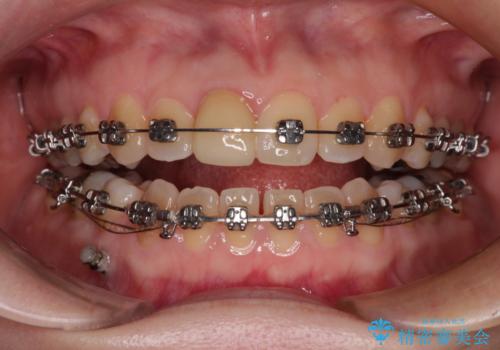

【モニター】後戻りでできた隙間 ワイヤー装置での再矯正

- メタルブラケット

- 学生時代に行った抜歯矯正の後戻りで、隙間ができてしまったことを気にして来院された患者様です。

マウスピース矯正を検討されていましたが、後戻りの隙間が非常に大きく、奥歯を前方に移動させる必要があるため、ワイヤー装置にて矯正治療を行うこととしました。

舌の突出癖が非常に強く、その影響で隙間ができてしまったので、舌のトレーニングをしっかりと行っていただきました。